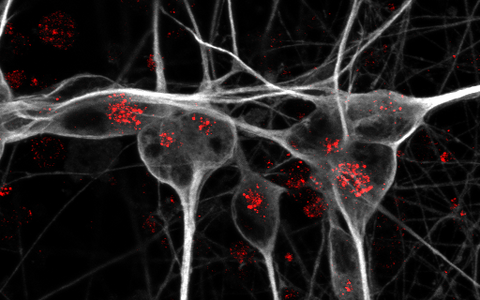

Detection of apoE receptor sortilin (red) in iPSC-derived human neurons (grey).

Detection of apoE receptor sortilin (red) in iPSC-derived human neurons (grey). Photo: Anna K Greda, Universität Aarhus